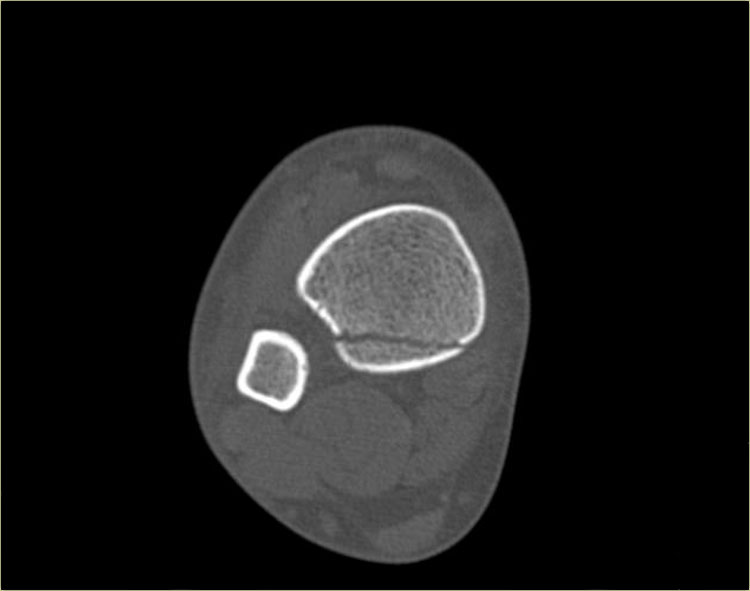

Đây là hình ảnh của một ca bệnh cực kỳ khó.

Bệnh nhân nữ bị bong gân cổ chân và đau cả hai bên trong và ngoài.

Bệnh nhân được bác sĩ đa khoa chuyển đến khoa Chẩn đoán Hình ảnh.

Kỹ thuật viên chụp các tư thế chuẩn gồm thẳng (AP), Mortise và nghiêng, sau đó trình bày cho bác sĩ X-quang, người đã khá băn khoăn khi đọc phim.

Hãy đọc hình ảnh trước, sau đó tiếp tục đọc phần giải thích.

Các dấu hiệu bao gồm:

-

Phù nề phần mềm cả hai bên trong và ngoài (mũi tên đỏ).

Đặc biệt, phù nề phía trong nên gợi ý khả năng chấn thương xoay ngoài – sấp (Weber C). - Đường thấu quang trên tư thế Mortise (mũi tên đen) và tư thế nghiêng. Dấu hiệu này nên gợi ý gãy tertius.

Bác sĩ X-quang quyết định chỉ định CT trước để xác định xem có thực sự có gãy tertius hay không.

Tiếp tục xem hình ảnh CT và bạn sẽ ngạc nhiên.

Hãy cuộn qua các lát cắt.

Thật đáng ngạc nhiên khi một mảnh tertius lớn như vậy lại rất khó nhìn thấy trên phim X-quang.

Cũng lưu ý phù nề phần mềm phía trong gợi ý đứt dây chằng bên trong (mũi tên).

Bạn có thể đoán được đây là loại chấn thương gì không?

Phù nề phần mềm phía trong và gãy tertius đều là dấu hiệu của chấn thương Weber C hoặc chấn thương xoay ngoài – sấp.

Do không thấy gãy xương mác trên phim X-quang cổ chân, phải có gãy xương mác cao.

Khi khám lâm sàng, có phù nề nhẹ phía trong và mặc dù bệnh nhân không than đau ở vùng cao hơn của cẳng chân, vẫn có điểm đau khi ấn vào xương mác.

Vị trí này được đánh dấu và phát hiện đường gãy.

Ca bệnh này minh họa tầm quan trọng của phù nề phần mềm phía trong cũng như dấu hiệu gãy tertius.

Theo phân loại Lauge Hansen, chúng ta có thể kết luận rằng bệnh nhân này đầu tiên bị đứt dây chằng bên trong (giai đoạn 1), tiếp theo là đứt dây chằng chày mác trước (giai đoạn 2), gãy xương mác cao (giai đoạn 3) và cuối cùng là bong mắt cá sau, tức là chấn thương xoay ngoài – sấp (PE) giai đoạn 4.

Trong phẫu thuật, cổ chân được xác định là không vững và vít cố định khớp chày mác đã được đặt vào.

Có chỉ định cố định gãy mắt cá sau vì mảnh gãy chiếm hơn 25% diện khớp của đầu dưới xương chày.